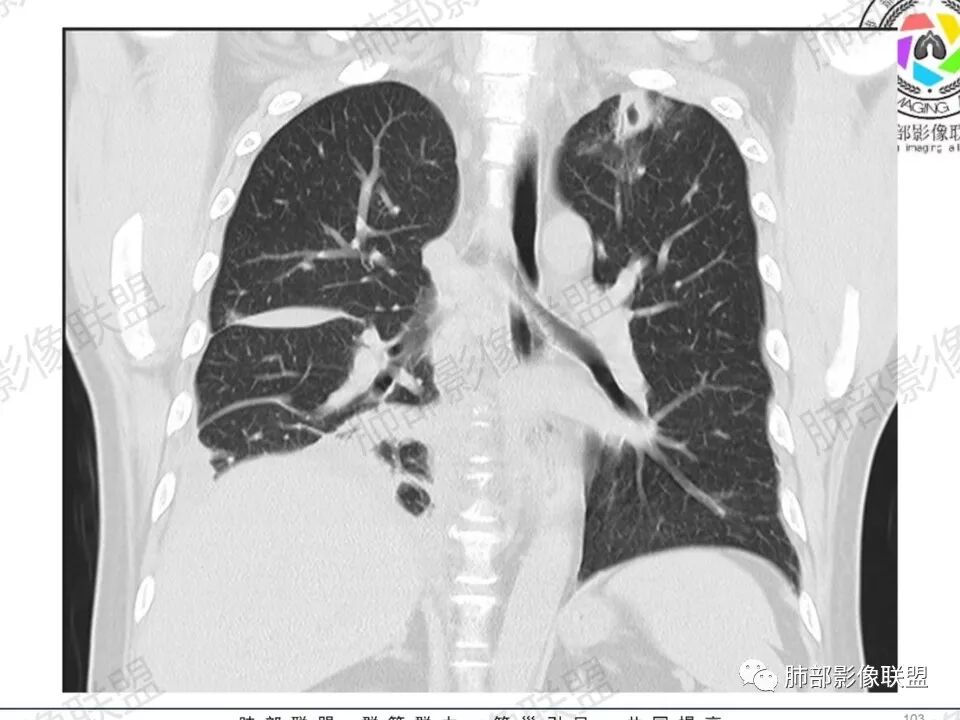

尘缘: @赵永兵 内蒙巴市临河妇幼影像科 左上肺也是胸膜下(胸膜顶下)的SPE。

@赵永兵 内蒙巴市临河妇幼影像科 支气管是从旁边经过,所以不是空洞,是胸膜下的脓毒栓。如果是结核空洞,应该与支气管相通(因为结核没有血播感染表现的时候,来源是气道,空洞应该与支气管相通),所以支气管从旁边经过,这病灶又在胸膜下,周围也没有干酪坏死。当然是SPE了。

空洞内壁光滑,偏心厚壁空洞,张力高

胸水,部分包裹

支持血道来源感染性病变,金葡菌肺炎首选